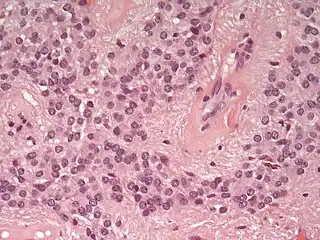

Los ependimomas se componen de células con núcleos regulares y ovoides o circulares. Por lo general se acompañan de una parénquima denso y fibroso haciendo que las células tumorales adopten una forma glandular y elongada que tienen cierto parecido al canal ependimal embriológico con vasos sanguíneos irrigando la neoplasia.[3] Los ependimomas extraespinales o extradurales pueden ser una forma muy inusual de teratoma.[4][5]